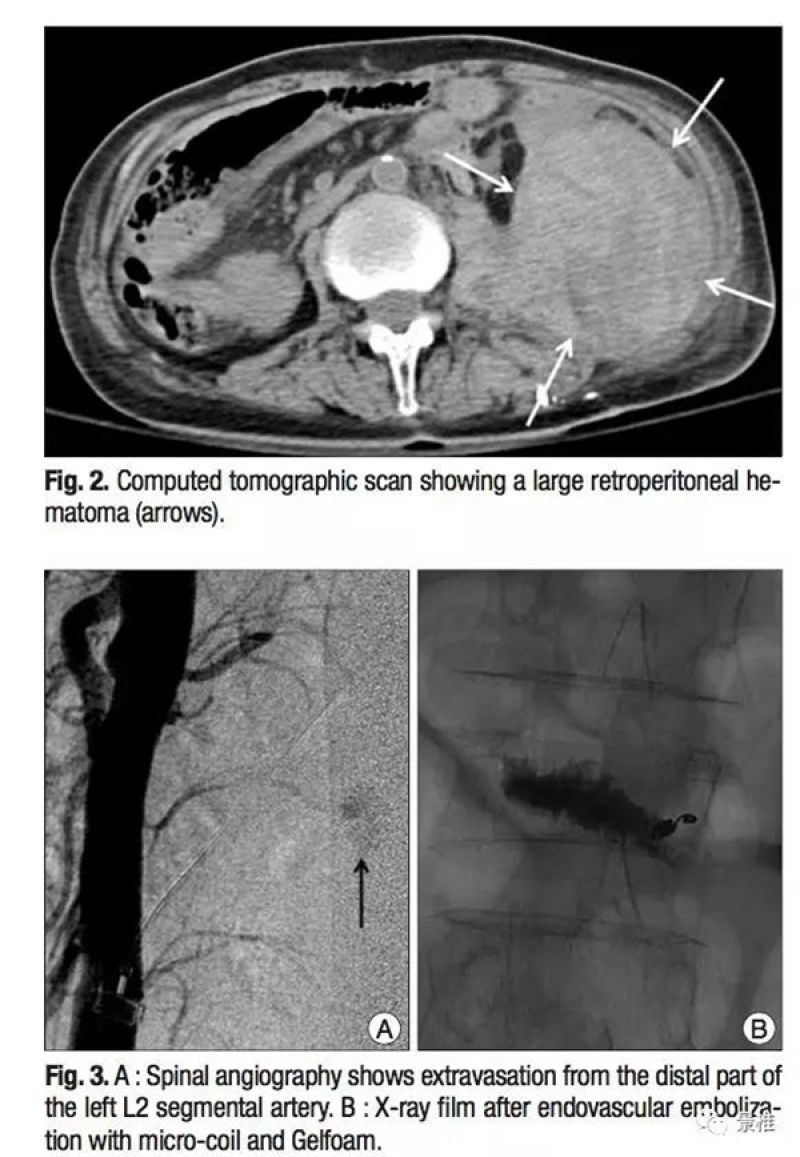

椎弓根外侧入路不走椎弓根,走椎旁。不伤神经,却有可能伤及椎旁节段血管。

该患者做完PVP术后失血性休克症状。复查CT发现巨大的腹膜后血肿。血管造影发现L2左侧节段动脉远端破裂,行栓塞修复。

三维CT显示椎旁节段动脉就在椎体旁正中走行,所以椎弓根外侧穿刺安全边界在椎弓根中线以上。